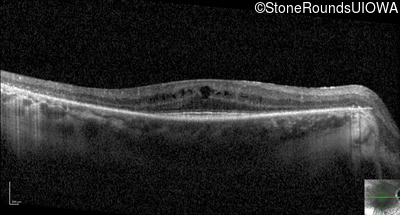

Optical Coherence Tomography - Left - 20/30 +2

Exemplar / OCT Stack

OCT Stack